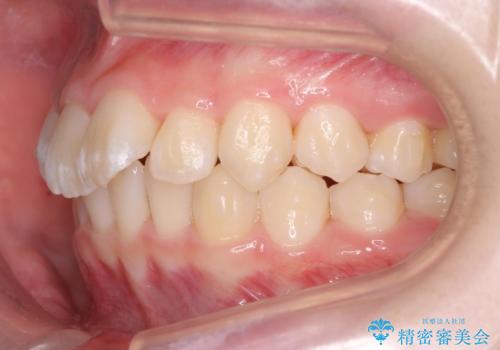

子供の出っ歯 生え代わりと成長期を利用して非抜歯で矯正

- 出っ歯を主訴に来院。

生え代わりを待ってから矯正を始めました。

特に右側のかみ合わせがずれていたため、上の奥歯を後ろに下げています。

下顎も前方に成長し、前歯のかみ合わせも同時に深かったのを浅くすることができました。